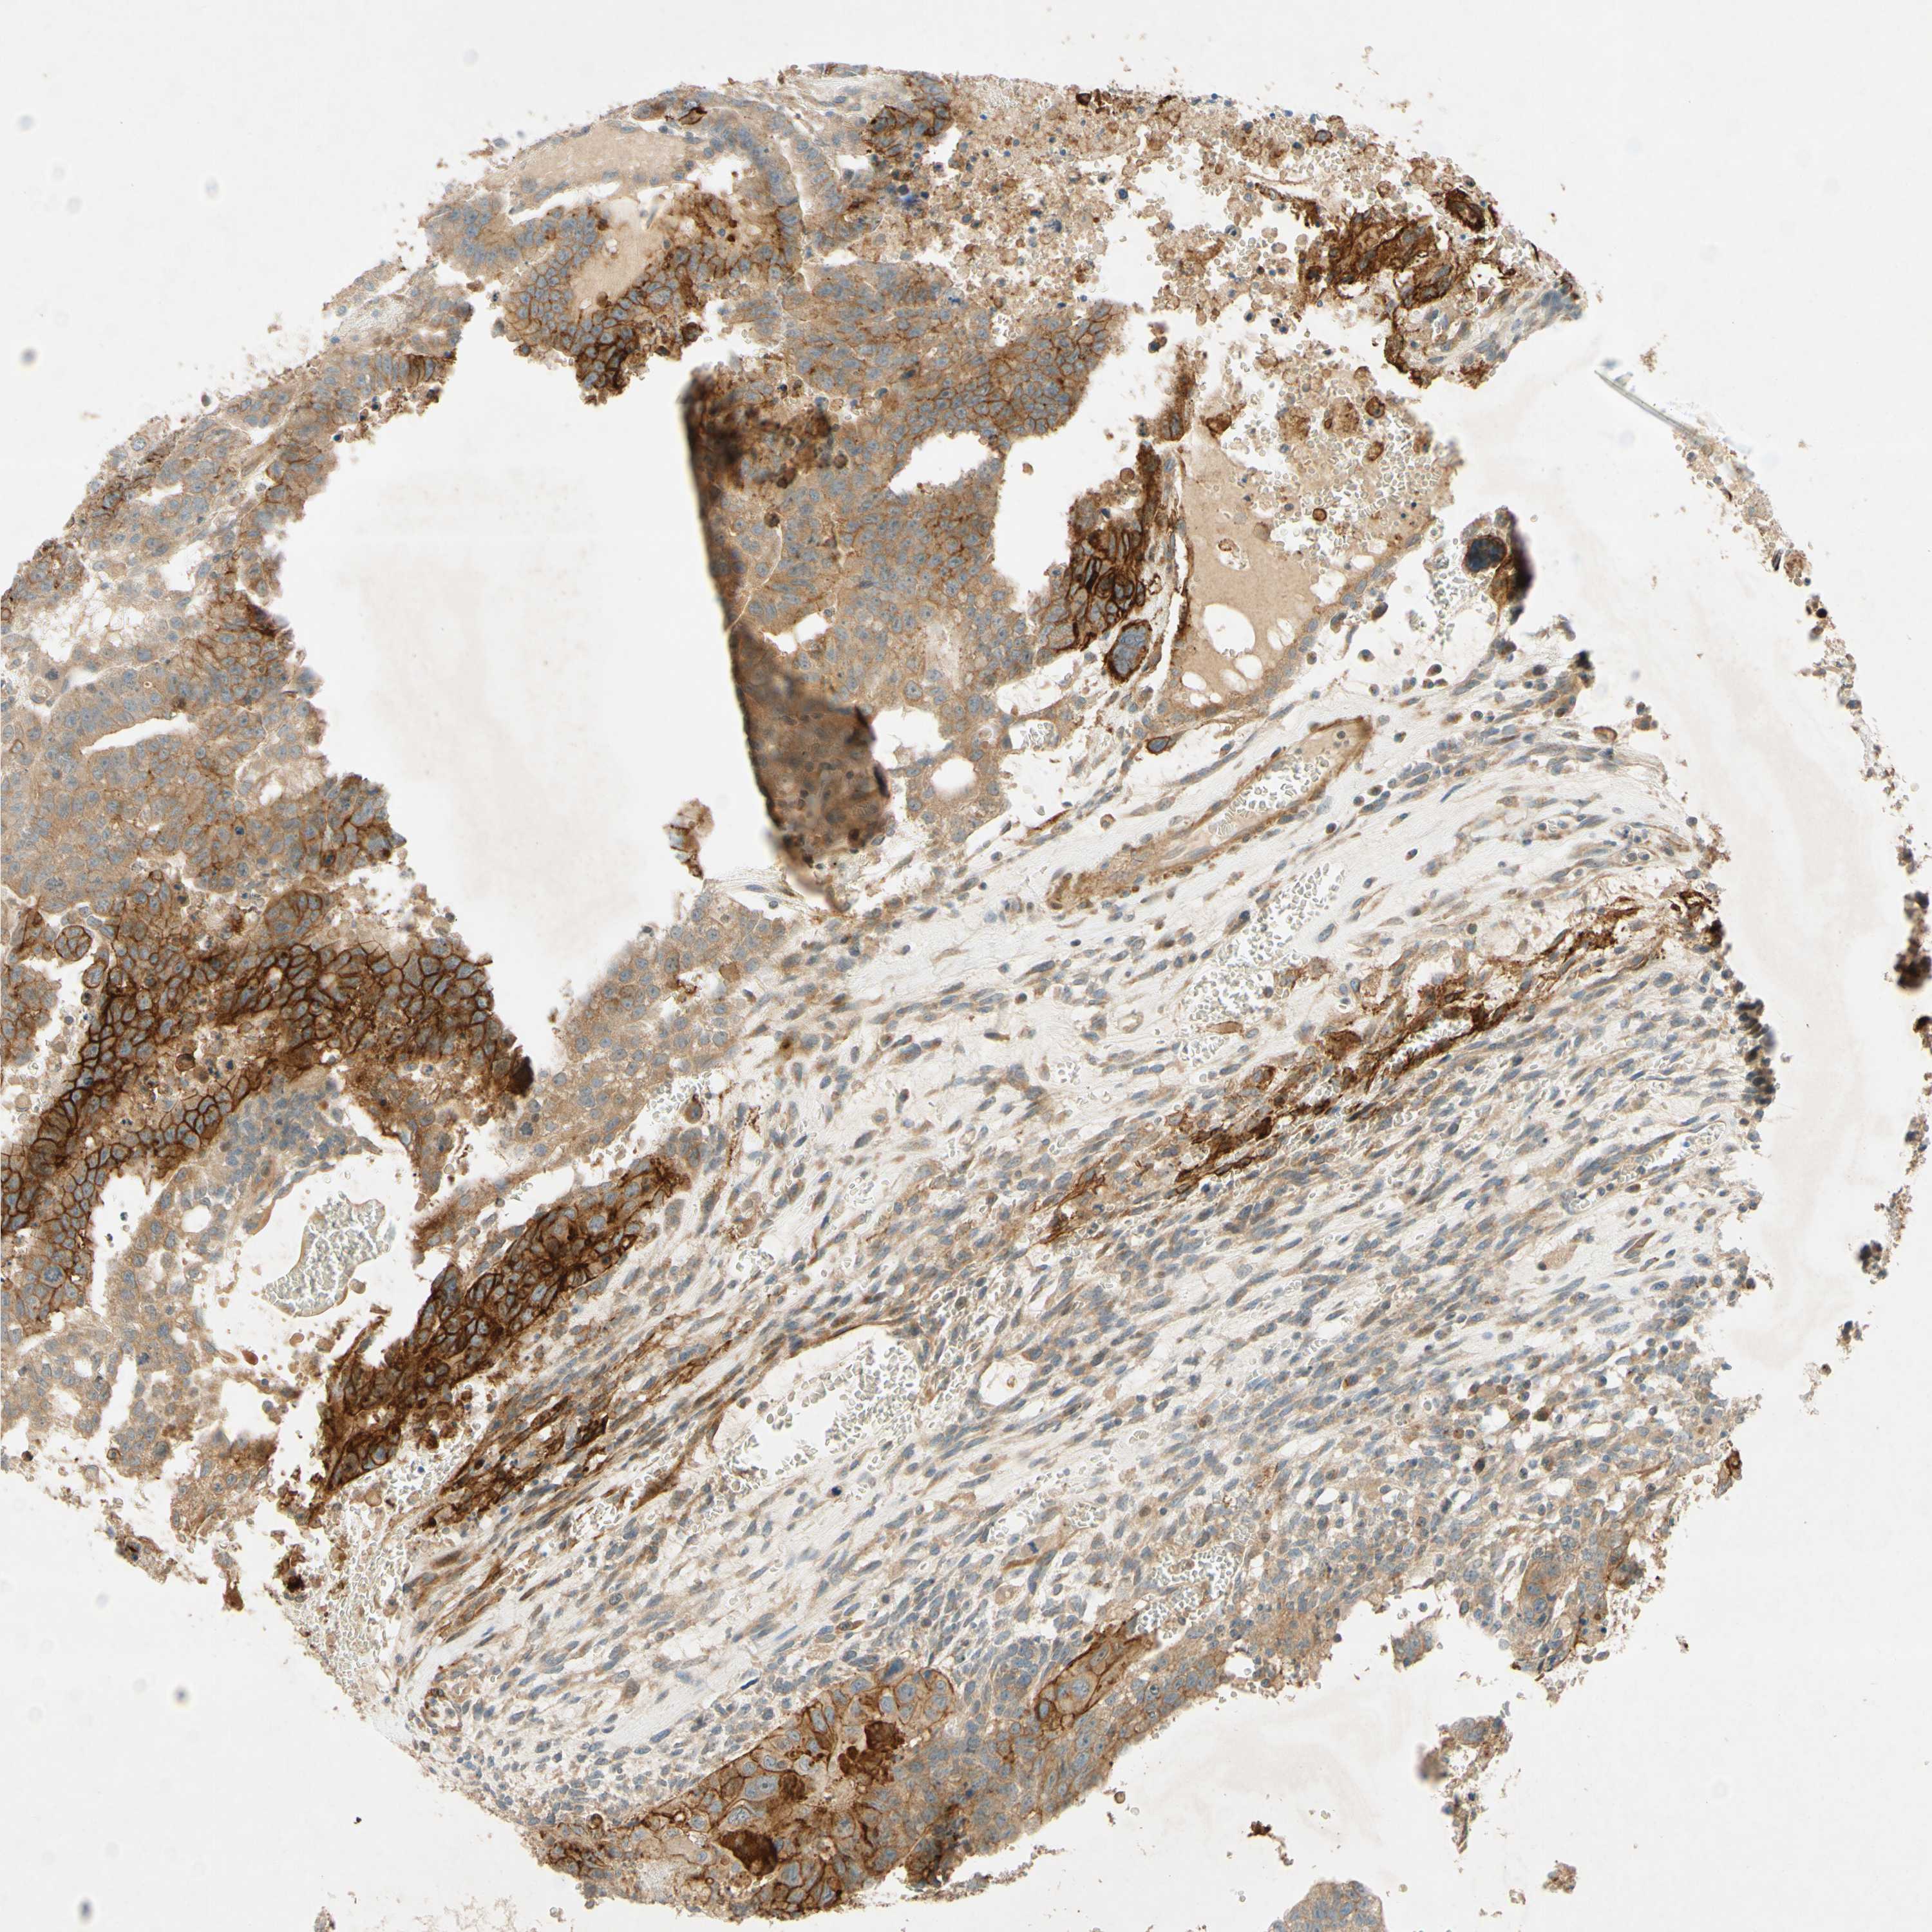

TESTIS CANCER - Protein expressioni

A mouse-over function shows sample information and annotation data. Click on an image to view it in a full screen mode. Samples can be filtered based on level of antibody staining by selecting one or several of the following categories: high, medium, low and not detected. The assay and annotation is described here.

Note that samples used for immunohistochemistry by the Human Protein Atlas do not correspond to samples in the TCGA dataset.

Antibody stainingi

Antibody staining in the annotated cell types in the current human tissue is reported as not detected, low, medium, or high, based on conventional immunohistochemistry profiling in selected tissues. This score is based on the combination of the staining intensity and fraction of stained cells.

Each image is clickable and will lead to virtual microscopy that enables deeper exploration of all samples and also displays staining intensity scores, fraction scores and subcellular localization as well as patient and tissue information for each sample.

Antibody HPA010738

Staining

High

Medium

Low

Not detected

Intensity

Strong

Moderate

Weak

Negative

Quantity

>75%

75%-25%

<25%

None

Location

Nuclear

Cytoplasmic/membranous

Cytoplasmic/membranous,nuclear

Carcinoma, Embryonal, NOS

Seminoma, NOS